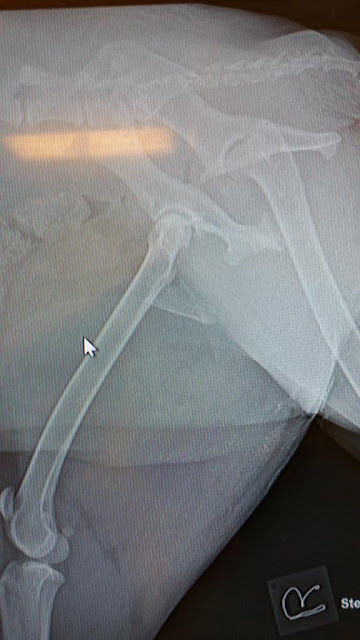

When the vet saw the extent of Baby’s injuries from the x-ray, he closed his eyes from the horrific image. One could not imagine the magnitude of the agony Baby is going through. Both Baby’s hips were crushed. When he further examined her, he noticed tire marks and huge bruises on the inside of her thighs and her legs. Her whole lower body was swollen from the impact and he had thought that her bladder was ruptured. The irresponsible driver must have been going at a high speed or not watching the road to be able to deliver such a lethal and disastrous impact to Baby. Those mere seconds of carelessness from an inconsiderate driver rendered a poor helpless innocent dog shriveled up and shuddering with tremendous pain. The injustice that raged in us when we see one of our own lying broken and defenseless is indescribable. The vet also had to insert a catheter as it was too painful for Baby to even pee. He had great difficulty inserting the catheter as her bladder was so swollen. It was only during the next day’s surgery that they realized that during the high impact, poor Baby’s bladder had been pushed and totally displaced! Despite being sedated, Baby cried softly while we discussed her situation. Pitiful Baby, confused, bewildered and scared out of her wits at her unfortunate predicament. The senior vet whom we consulted said had she not been saved in time, she would have died a slow painful death by the roadside.

A surgery would set us back about $8000/- to insert metal plates and pins in both her hips and an estimated 10 days stay at the vet. The vet had said she would most likely need to stay 3 to 4 weeks as she would require daily wound cleaning and emptying of her pee bag, etc but since we can ill afford the $8000/-, we are praying we will find a foster upon her discharge.

Despite the long road to recovery, Baby would have a shot at a second chance in life and would be able to run and jump one day again. It would be a very complicated surgery as the vet would need to ensure that the nerves are not damaged in the midst of the surgery. However it is the news that Baby would be saved that lifted our spirits a little. Such a poor sweet innocent life should not be taken away so abruptly in such a grisly manner. Seeing Baby cling on to life fueled our strong desire to get her through this excruciating part of her journey. Her puppy eyes, although drained out from the agonizing pain from her injuries, seem to have the tiny glimmer of hope that the worst is over for now. It was fate that Mr R discovered her in time and got her to us. It is now Hope that we will cling on to, to raise funds for Baby’s surgery and a smooth recuperation for her. The journey for her is going to be fraught with difficulties. It is her unwavering desire to live that enabled her to cling on till now.

She has undergone one surgery (on 7 July 2015) to push her displaced bladder back in place. Thankfully her bladder was not ruptured. She will undergo her second surgery (on 9 July 2015) to repair both her fractured hips.